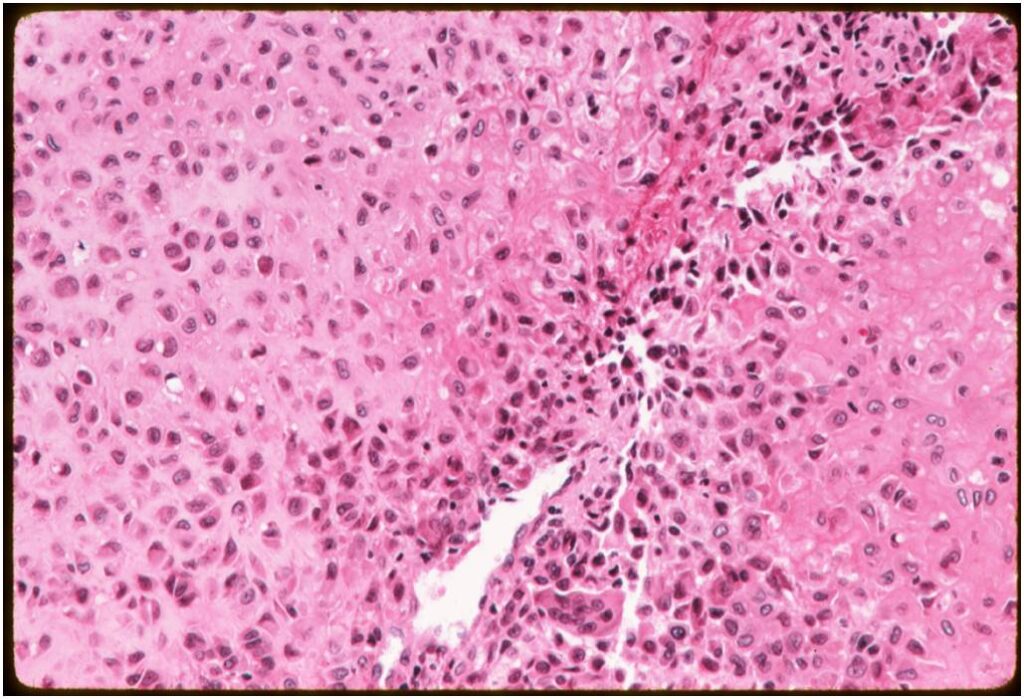

Microscopic Pathology

- Variable appearance depending on percentage of cells, necrosis, cartilage matrix formation and ABC change

- Chondroid matrix in up to 15% of tumor

- ABC component 5-15% of tumors

- The tumor is composed of chondroblasts that have a distinct, thick cell membrane. The thick cell membrane gives it a “Chicken Wire Fence Appearance,” especially when the cell membranes are calcified